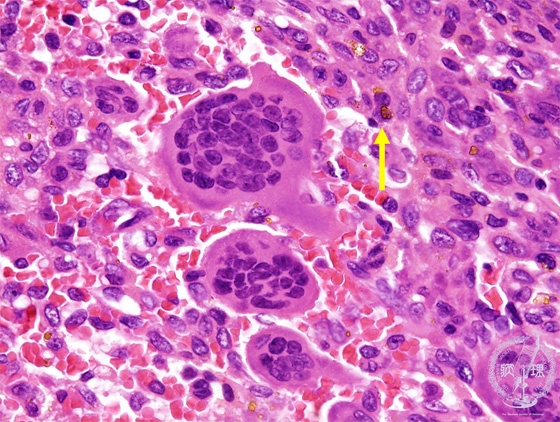

- (9)Giant cell tumor of the bone

Microscopic view (HE; high power view): The number of the multiple nuclei is up to dozens. Hemosiderin deposition is also seen.